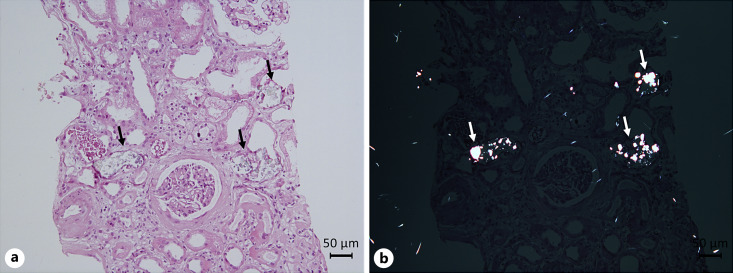

Summary: Disruption to any key step in the oxalate pathway including abnormal endogenous generation, ingestion of abnormally high dose of oxalate, increased absorption or attenuation of oxalate degradation in the gut, and reduced excretion through the kidney may lead to disrupted oxalate homeostasis. Oxalate nephropathy is mainly caused by hyperoxaluria. Oxalate crystal deposition in the kidney is usually accompanied with tubular toxicity, obstruction, interstitial fibrosis, and tubular atrophy. The mechanism of oxalate-induced renal injury has not been fully clarified. Evidence from both in vivo and in vitro studies shows that NLRP3 inflammasome activation and macrophage infiltration are involved in the processes of crystal adhesion, aggregation, and elimination and promote intrarenal inflammation and renal fibrosis. Novel treatment strategies have been developed and targeted therapies tested for oxalate nephropathy.

Key messages: Prompt diagnosis and management may help to reduce the deposition of calcium oxalate crystals in the kidney. Further studies are needed to clarify the underlying mechanisms to help develop more targeted therapies for oxalate nephropathy.